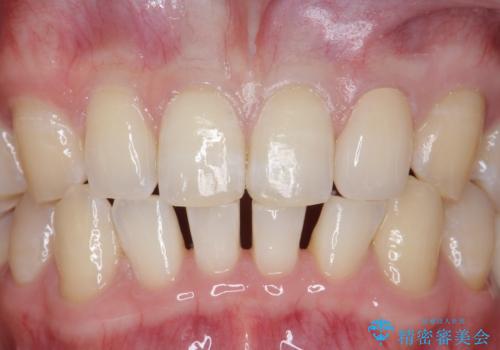

- 上顎前歯のすきっ歯が気になるといらっしゃった方の症例です。

上顎前歯のみの治療を希望されたので、部分矯正を行いました。

左上2の矮小歯はオールセラミッククラウンによる補綴を行いました。

今回用いたオールセラミッククラウンは、ジルコニアフレームという白い素材の上にセラミックを盛っているため審美性が非常に高いのが特徴です。

またジルコニアは人工ダイヤモンドの材料にも使われているほど高い強度を持っており、そのためオールセラミッククラウンは審美性だけでなく、奥歯やブリッジの補綴も可能とするクラウンです。